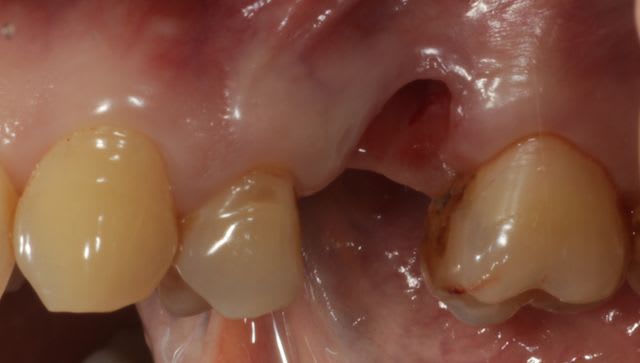

Bon j'ai extrait la dent et maintenant y a un gros trou.